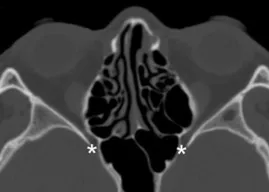

Coronal plane image of cribriform plate (asterisks).

Axial CT of foramen rotundum (asterisks).

Axial CT of foramen rotundum (asterisks).